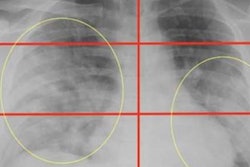

The MAIL2.0 AI model provides a probability score of 0 (low probability of COVID-19) to 1 (high probability) after analyzing chest radiographs. In this radiograph of a COVID-19 case, the model's probability score of 0.985 indicated a high probability of having the disease. Image courtesy of Dr. Michael Kuo.The model significantly outperformed the radiologists (p < 0.001). Delving further into the results, the researchers found that the MAIL2.0 model correctly identified 40 (81.6%) of the 49 COVID-19-positive cases that were missed by the radiologists. On the other hand, the radiologists spotted two (18.2%) of the 11 COVID-19-positive cases that the model had missed.